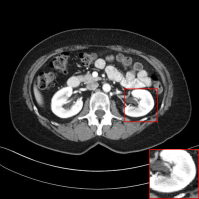

Figure 4: Qualitative results of our method and other baselines on Mayo Clinic Low Dose CT dataset. (a) Real low-dose. (b)-(f) Results of each methods. (g) Real normal-dose. As shown in the highlighted red box, the reconstructed image by our method has few noise and artifacts. The display window is [160,240]160240[160,240] HU.

Denoising on Low-Dose CT

Since Computed Tomography (CT) helps to diagnose abnormalities of organs, CT is widely used in medical analysis. Reducing the radiation dose in order to decrease health risks causes noise and artifacts in the reconstructed images. Like the real-world noise, the noise distributions of the reconstructed image are difficult to model analytically. Therefore, we adopt a CT dataset authorized by Mayo Clinic [Moen etย al.(2021)Moen, Chen, Holmesย III, Duan, Yu, Yu, Leng, Fletcher, and McCollough] to evaluate the generalization ability of our method on real-world noise. Mayo Clinic dataset consists of paired normal-dose and lose-dose CT images for each patient. The Normal-Dose CT (NDCT) and the Low-Dose CT (LDCT) images correspond to clean and noisy images, respectively. For the training, we obtain 2,850 images in 512ร—512512512512\times 512 resolution from 20 different patients. We construct 1,422 LDCT images from randomly selected 10 patients as a noise set and 1,428 NDCT images from the remaining patients as a clean set for unpaired training. For the test, we obtain 865 images from 5 different patients. As shown in Table 2, our method achieves the best and the second-best performance in PSNR and SSIM, respectively. Note that our model trained on the unpaired dataset outperforms the RED-CNN trained on the paired dataset in PSNR. It indicates that our method can be more practical in medical analysis where obtaining paired datasets is challenging. We also compare the qualitative results with other baselines. As shown in Figure 4, other methods tend to generate artifacts or lose details. On the other hand, our method shows a reasonable balance between noise removal and image quality. More qualitative results are provided in the supplementary material.